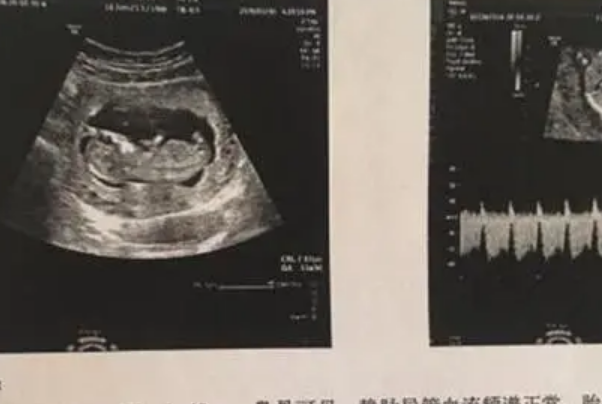

问题描述: 我现在已经来到了怀孕中期了,上回去医院产检的时候医生看着我的B超单子说,我的胎儿是头大腿短的状况,我回家之后将这个消息跟我妈说了之后,她非常自信地跟我说,医生这是在暗示你将来会生一个男孩,我有点不太明白,因为我知道医生一般都是通过生殖器来观察性别的,所以就想问问大家,胎儿出现这种情况是生男孩的概率更大,还是生女孩的概率更大呢?

女性在怀孕中晚期的时候做产检需要定期做彩超检查,这个时候常规会测量胎儿的双顶径、头围和股骨长径,并以此来估计胎儿的发育跟孕周是否相符,如果双顶径和头围稍大于孕周而双顶径稍短于孕周,即胎儿出现头大腿短的现象,这种情况可能是下面几种原因导致的: